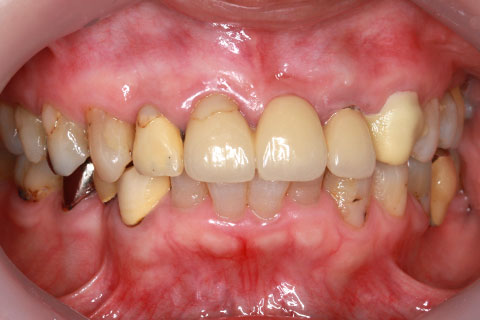

• オールセラミックの症例3

治療前

治療後

古くなった被せをジルコニアセラミックスで治療。

年齢・性別

60歳女性

治療期間

1ヶ月

抜歯

なし

治療費

35.2万円

備考

古くなった被せを新たなセラミックス冠にする。

治療内容

歯質を削除し、セラミック冠をセメント合着

施術の副作用(リスク)

知覚過敏、歯髄炎、荷重負担